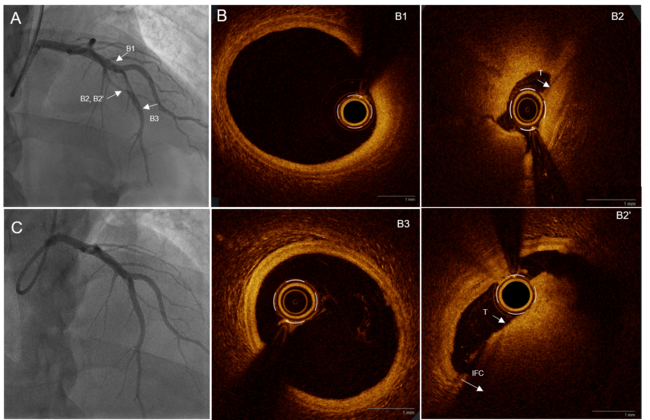

Video 1. Initial angiography showing 99% subocclusive stenosis of the mid-left anterior descending artery and impaired flow.

Video 2. Optical coherence tomography acquisition with high-definition automated analysis (Ultreon software [Abbott]) demonstrating an intact fibrous cap (plaque erosion) and real-time luminal measurements (minimal lumen area: 2.6 mm²) following mechanical reperfusion.